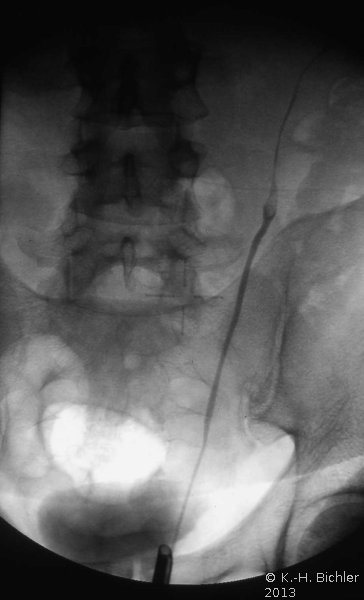

Die Röntgenübersicht der Niere und ableitenden Harnwege zeigten keinen Anhalt für Konkrement. Im Ausscheidungsurogramm eine "stumme Niere" links (Abbildung 19a). Bei der retrograden Sondierung links fand sich keine Abflussbehinderung (Stein oder Stenose) (Abbildung 19c). Im MCU kein Anhalt für Reflux (Abbildung 19b). Im Nierenfunktionsszintigramm MAG3 wurde eine seitengetrennte Funktionsverteilung von rechts zu links wie 93% zu 7% festgestellt. Zur Abklärung eventueller Gefäßalterationen erfolgte eine Renovasographie mit dem Nachweis einer langstreckigen Stenose der linken Arteria renalis (Abbildung 19d). Wegen des Verdachtes auf eine generalisierte Arteriitis wurden Angiographien weiterer Gefäßgebiete durchgeführt: Dabei fanden sich eine geringgradige Einengung der infrarenalen Aorta und der linken Arteria subclavia.